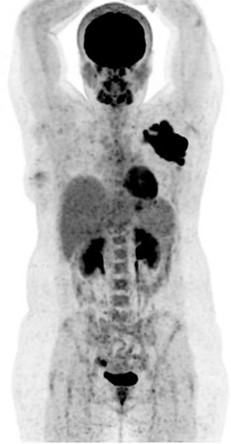

♦ Le TEP Scanner

L’examen : Il faut être à jeun depuis 4 à 6 heures. Une fois arrivé dans le service de médecine Nucléaire, on vérifie la glycémie, branche la perfusion, injecte le radiotraceur puis repos pendant 60 min (fixation tissulaire) et enfin acquisition des images pendant 20 min avec les bras au-dessus des épaules.

IL est utile dans la personnalisation du traitement : permet l’évaluation précoce du traitement dans le cas des Hodgkin ou des grandes cellules B, en fin de traitement selon le type de lymphomes. Il permet également de donner des informations sur une éventuelle transformation en lymphome de haut grade, ou sur une atteinte osseuse. Il ne remplace en aucun cas une biopsie.